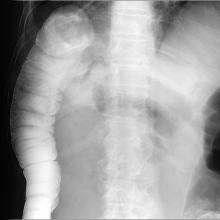

根據病史、症狀體徵、X線檢查可發現膈下游離氣體、腹部超聲、CT等檢查,不難診斷。但診斷過程中一定要明確穿孔部位、穿孔病因來指導治療。